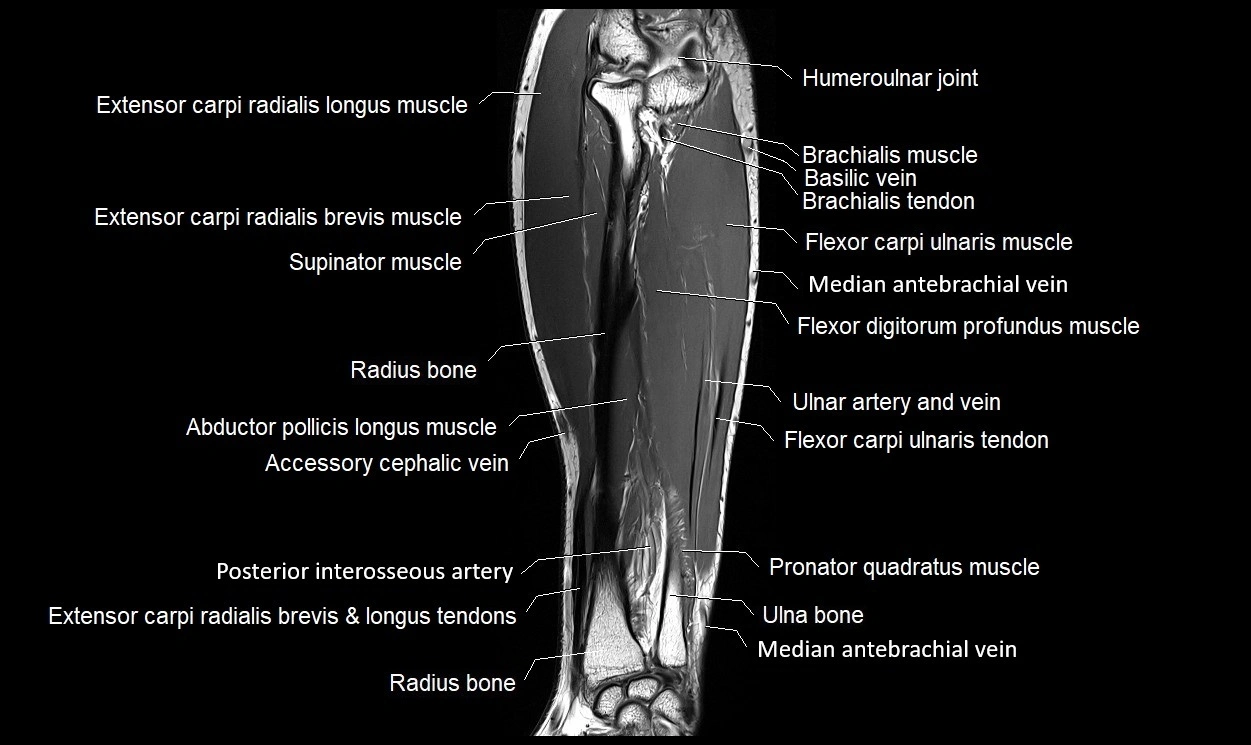

MRI images

image